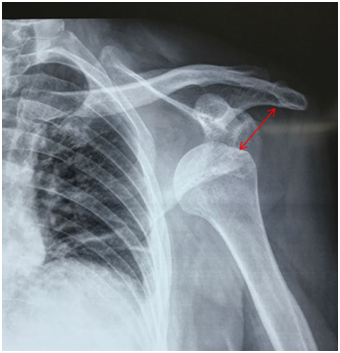

🔹肩关节半脱位(患侧肌肉无力致关节错位)